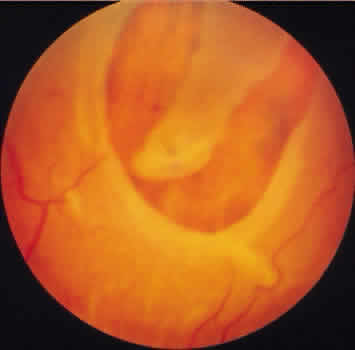

Retinoschisis associated with a bullous architecture and prominent reticular cystoid degeneration has been termed reticular degenerative retinoschisis. Reticular degenerative retinoschisis can be distinguished from typical degenerative retinoschisis by the large extent of retinal involvement, a round or ovoid configuration with bullous elevation of the extremely thin inner layer, and an irregular, pitted outer layer (Figs. 20 and 21). Typical cystoid degeneration is always present anterior to the schisis; reticular cystoid degeneration is usually prominent at some site in the involved eye. Blood vessels coursing through the inner layer give it an arborizing reticular pattern on contact lens biomicroscopy. The intraretinal cavity is optically empty; the outer wall is irregularly excavated to produce a pocked or honeycomb appearance. Round or ovoid holes are often present in the outer retinal layer; they are single or multiple, frequently large, and usually associated with a rolled posterior edge.13

Fig. 20. Reticular degenerative retinoschisis. Note reticulated, highly elevated, inner wall with a conspicuous delicate vascular pattern. Radial columns of the retina are completely disrupted within the region of bullous elevation, and the retinoschisis extends posterior to the equator. (× 18.)

Fig. 21. Clinical appearance of reticulardegenerative retinoschisis: diagram of involved area and photographs of ocular fundus showing optic disc, macula, and posterior portion of the schisis. These illustrate outer layer retinal breaks, adjacent retinal pigment epithelium abnormality, and a lo-calized nonrhegmatogenous retinal detach-ment.

Microscopic sections demonstrate the extremely attenuated, blood vessel-containing inner layer composed of the internal limiting membrane and remnants of the nerve fiber layer (Fig. 22). The honeycomb appearance of the outer layer corresponds to irregular excavations. In some areas, the outer layer is made up of outer plexiform, outer nuclear, external limiting, and rod and cone layers; in other areas it is reduced to only the external limiting and the rod and cone layers; round or ovoid holes may be present (Fig. 23).

Fig. 22. Reticular degenerative retinoschisis. Note complete loss of radial supporting columns of retina and marked elevation of delicate inner wall, which contains fine blood vessels. Outer wall shows periodic exaggerated thinning. (Hematoxylin-eosin; × 60.)

Fig. 23. Reticular degenerative retinoschisis with hole in outer wall and localized retinal detachment. Margins of hole are rolled and covered by a garland of degenerating photoreceptor outer segments. (Hematoxylin-eosin; × 250.)

Reticular degenerative retinoschisis is evident in 1.6% of adult patients, is bilateral in only 16% of these, and thus is noted in 0.95% of adult eyes (see Table 3). The lesion is found most commonly in the inferior temporal quadrant. A band of typical cystoid degeneration always separates the schisis from the ora serrata; the schists usually reaches the equator and often extends appreciably into the posterior retina.

On contact lens biomicroscopy, many retinal blood vessels present irregular contours, telangiectases, occluded segments, and microaneurysms. Between these vessels, the inner wall has a finely textured appearance and variable white, glistening particles on the vitreous side. The outer retinal wall is best seen when scleral depression produces a “white with pressure” phenomenon and reveals the honeycomb appearance. The retinal pigment epithelium often has a granular, salt-and-pepper appearance, and outer-layer retinal breaks are common. These breaks are particularly likely near the anterior and posterior margins of the schisis.